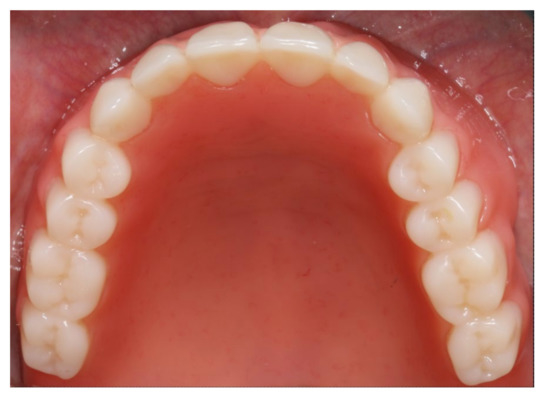

Inserted implant-supported overdenture in the lower jaw.

Figure 20.

Inserted complete denture in the upper jaw.

Figure 21.

Anterior view of the inserted dentures in centric occlusion.

During the final appointment, the Locator abutments were tightened with torque (0.35 Nm) and the dentures were inserted. The attachment patrices were equipped with inserts producing intermediate retention (green). Occlusion, extension, retention, and aesthetics were carefully controlled and adjusted where appropriate (Figure 19, Figure 20 and Figure 21). Both dentures featured excellent retention and fit. Finally, the patient was instructed regarding insertion, removal, and maintenance of the dentures. After one week, the patient was satisfied with the new prostheses and no complications were reported or identified.